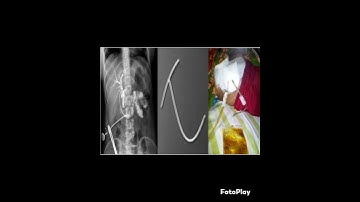

Neonatal Cholangiogram NEO